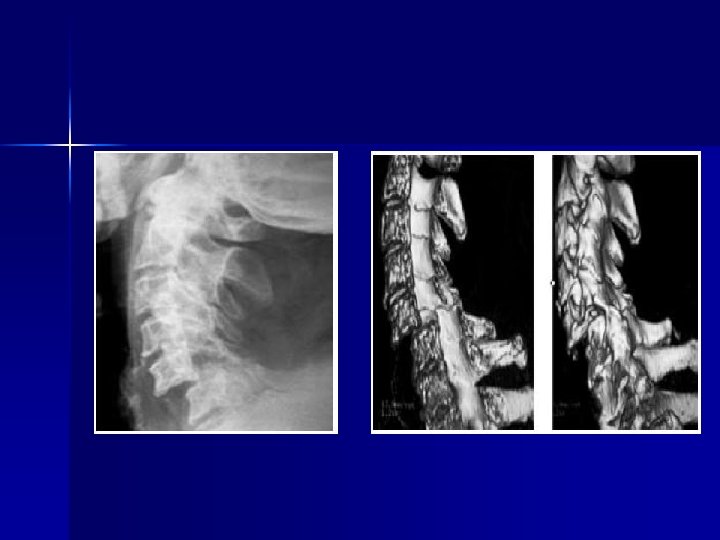

CUELLO Rx cervicales: -AP y laterales -Odontoides -Rx dinámicas: flexión y extensión para descartar lesiones ligamentos n TAC (Scan cervical): -Si hay sospecha de lesión n